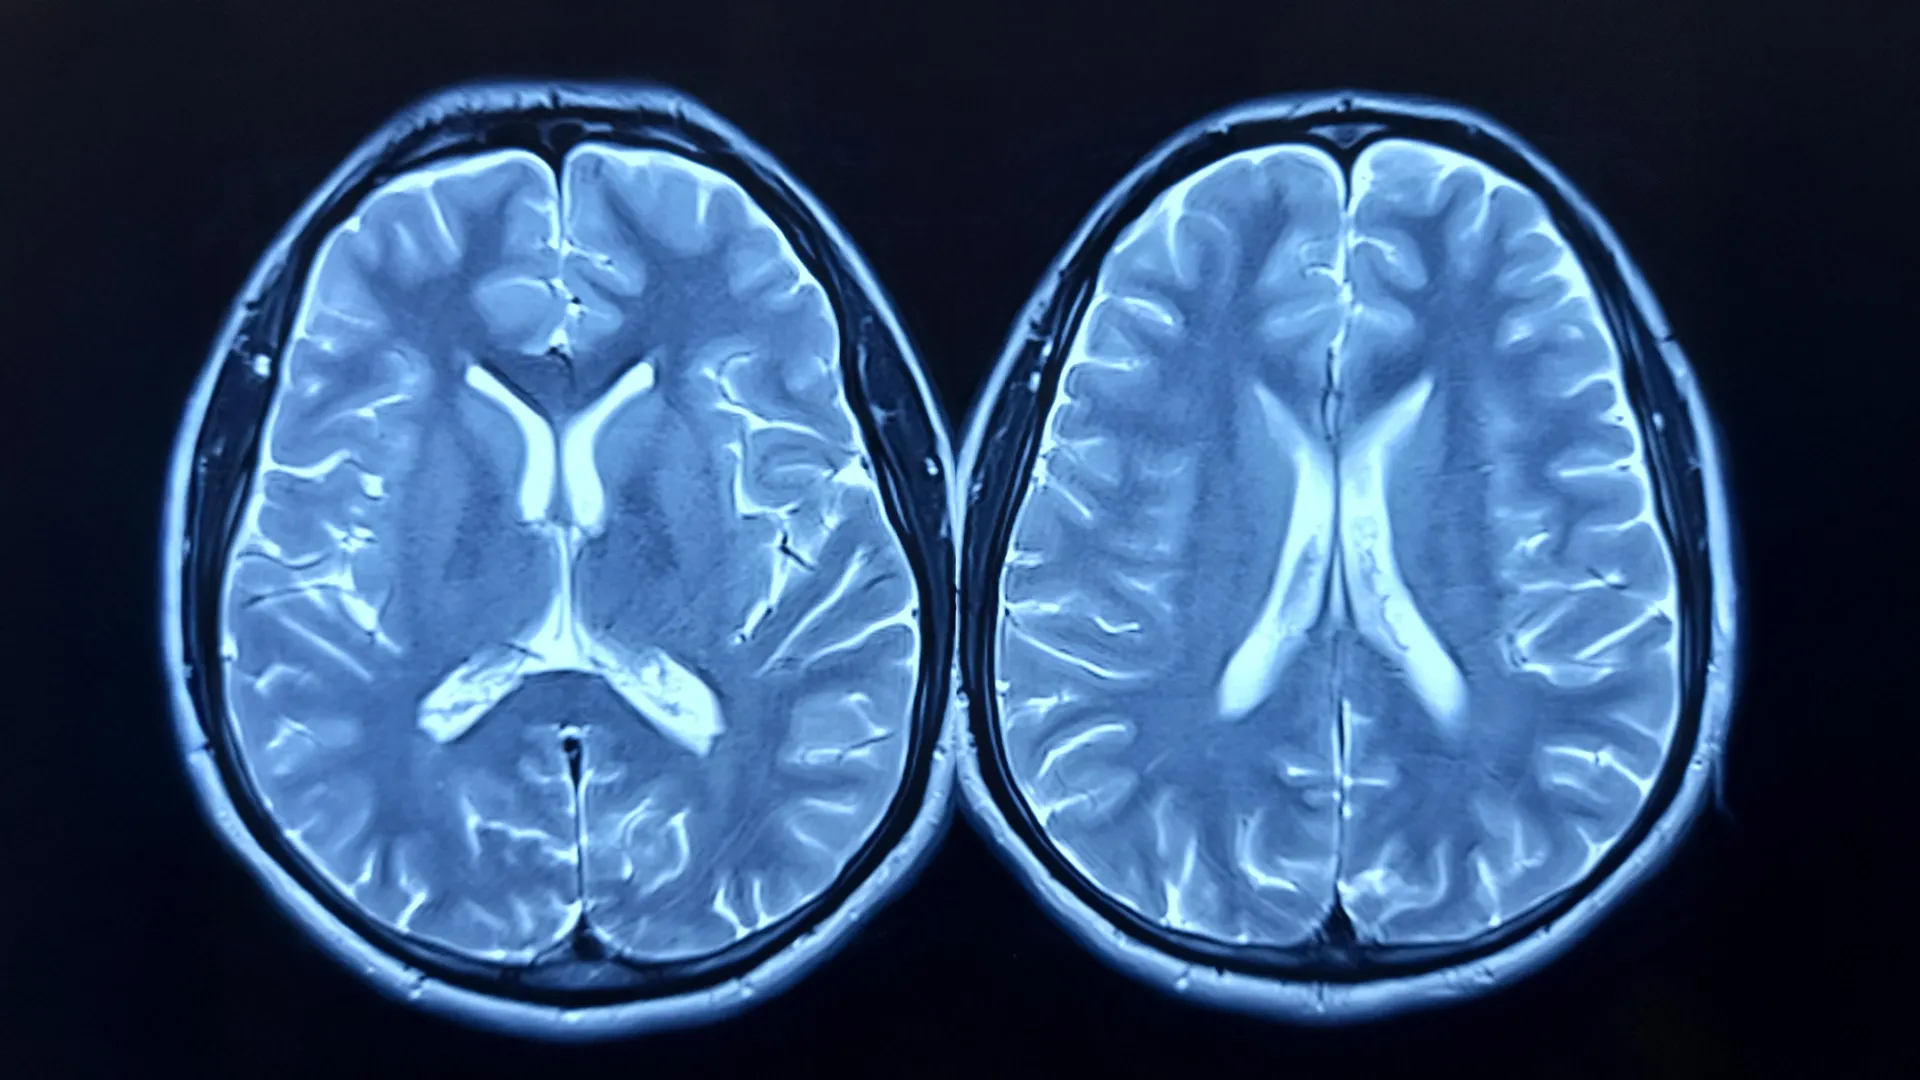

The scientific endeavor, detailed in the latest issue of the Journal of Sport and Health Science, set out to determine if the adoption of a regular aerobic exercise routine could either decelerate or even reverse the progression of what researchers term "brain age." This concept is assessed through sophisticated magnetic resonance imaging (MRI) techniques, which provide an estimation of a brain’s apparent age relative to an individual’s chronological age. A disparity indicating an older brain, quantified as a higher brain-predicted age difference (brain-PAD), has been previously associated with diminished physical and cognitive capabilities, as well as an elevated mortality risk. Dr. Lu Wan, the lead author and a data scientist at the AdventHealth Research Institute, highlighted the significance of the findings, stating, "We discovered that a straightforward exercise program, aligned with current health recommendations, can result in a discernible reduction in brain age within a mere twelve months." She further elaborated on the implications for public health, noting, "Many individuals harbor concerns regarding the preservation of their brain health as they advance in years. Studies like this provide encouraging insights rooted in accessible, everyday behaviors. While the absolute magnitude of these changes may appear modest, even a one-year shift in brain age can accrue substantial benefits over the span of several decades."

To quantify the impact of the exercise intervention on brain structure, researchers employed MRI scans at the commencement of the study and again following a 12-month period. Concurrently, cardiorespiratory fitness was assessed through measurements of peak oxygen uptake, commonly referred to as VO2peak, providing a physiological benchmark of participants’ fitness levels. This dual approach allowed for a comprehensive evaluation of both structural brain changes and functional fitness improvements.

Upon the conclusion of the year-long trial, the comparative analysis between the two groups revealed distinct and compelling outcomes. Participants who actively engaged in the exercise program demonstrated a statistically significant decrease in their estimated brain age. In contrast, individuals in the control group exhibited a slight, albeit not statistically significant, increase in their brain age. On average, the exercise group experienced a reduction in their brain-PAD by approximately 0.6 years, indicating that their brains appeared younger at the study’s end. The control group’s brains, conversely, appeared approximately 0.35 years older. When directly compared, the cumulative difference in brain age between the two groups was substantial, approaching a full year in favor of the participants who had followed the exercise protocol.